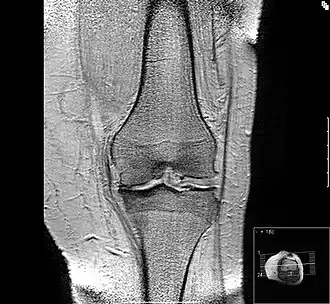

Mediales Kompartiment

In diesem Bild ist erkennbar, dass der Knorpel im innenseitigen (medialen) Bereich des Gelenkes aufgebraucht ist und im medialen Bereich des Schienbeinkopfes der unter dem Knorpel gelegene Knochen verdichtet ist. Dies wird „sklerosiert“ oder „eburnisiert“ genannt. Sowohl im seitlichen (lateralen) als auch im medialen Gelenkanteil ist es zu osteophytären Reaktionen gekommen. Der Körper versucht, durch eine Verbreiterung der Auflagefläche den auf den Gelenkknorpel lastenden Druck zu mindern. In der höheren Auflösung sind auf diesem Bild die Muskelzüge um das Knie deutlich zu sehen, in der verkleinerten Abbildung kommt das nicht zur Darstellung. Durch die „Höhenminderung des medialen Gelenkspaltes“ (klinischer Jargon, gemeint ist die Höhenminderung des Knorpels) kommt es zu einer Fehlstellung des Kniegelenkes, das Bein weicht in die Varus- oder O-Fehlstellung ab. Die Lotlinie vom Hüftkopf durch das Sprunggelenk wandert aus dem Zentrum des Knies in Richtung mediales Kompartiment aus, der Auflagedruck in dem schon verschlissenen Teil des Gelenkes nimmt weiter zu, das Krankheitsbild verschlimmert sich selbst.

Die Darstellungstechnik ist etwas anders als auf den oberen Bildern, der Reizerguss - im Prinzip Wasser - kommt hier weiß zur Darstellung. Zu sehen ist die Verteilung der Gelenkflüssigkeit (Synovia), dazu zeigen sich, besonders am oberen Pol der Kniescheibe, Osteophyten.